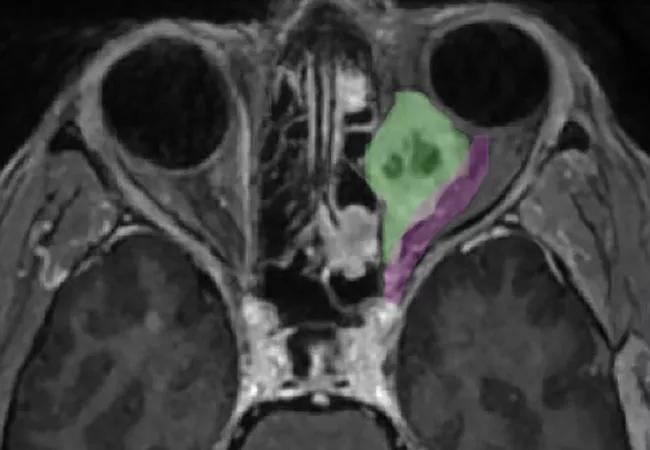

A 54-year-old woman with left eye pain, proptosis and limited ocular motility was evaluated at a non-Cleveland Clinic hospital. Following imaging and a transcranial biopsy, she was diagnosed with a GLI1-amplified spindle cell tumor behind her left eye.

This type of tumor, while rare, previously had been reported in various head and neck sites but never in the eye. In addition to its rare presentation, the tumor was uniquely positioned, spanning from the posterior globe deep into the orbital apex.

1. Drs. Recinos and Sindwani used a four-hand, endoscopic, endonasal approach to create a corridor through the sinuses to access the intraconal component of the tumor. By going through both nostrils, they gained access to the deep compartment of the eye and dissected the posterior portion of the tumor in the orbital apex.

2. Dr. Singh used a lid-split approach, entering through the eyelid, to release the anterior portion of the tumor from the ocular muscles, globe and optic nerve.

3. Dr. Singh pushed the freed anterior aspect of the tumor into the patient’s sinuses, where Drs. Recinos and Sindwani retrieved the entire mass and delivered it through the patient’s nose.

“Normally, we use the corridor between the medial and inferior rectus muscles of the eye to gain access to orbital tumors,” says Dr. Recinos. “In this case, the tumor sat superior to the medial rectus, a much more challenging position. So, we developed a corridor above the medial rectus muscle and were aided by an anterior dissection by Dr. Singh.”